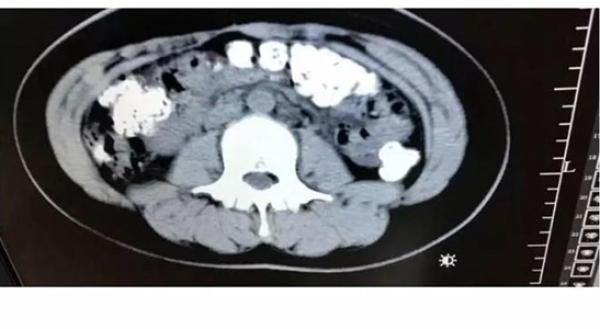

前些日子,小沈突然肚子疼,而且最近5天都无法排便,吃不下东西。她赶紧跑到医院去挂了急诊,结果照了个CT发现,她的胃肠道里,布满高密度颗粒状阴影,疑似珍珠奶茶里的“珍珠”,估计有百余颗。paz灵异岛|www.lingyidao.com